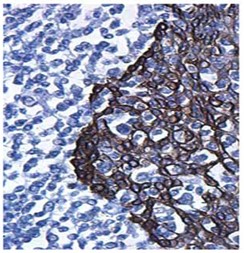

常规的免疫组化操作是把烤片后的石蜡切片经2-3次二甲苯、多次梯度酒精进行脱蜡水化,随后进行相应的抗原修复流程,耗时长,而且二甲苯具有较强的挥发性,长期吸入将会给技术人员的健康带来隐患。基因科技充分考虑病理科的现状和困扰,研发出新型脱蜡抗原修复缓冲液,该系列产品适用于石蜡切片的脱蜡和抗原热修复(柠檬酸/ 枸橼酸、EDTA),将常规的脱蜡、抗原修复、水化三个步骤合而为一。不仅节省实验时间和步骤,更重要的是改善了实验环境,减少了有机溶剂对操作人员健康的危害,同时,脱蜡效果与二甲苯脱蜡效果相当(见下图)。

二甲苯处理 脱蜡修复液处理